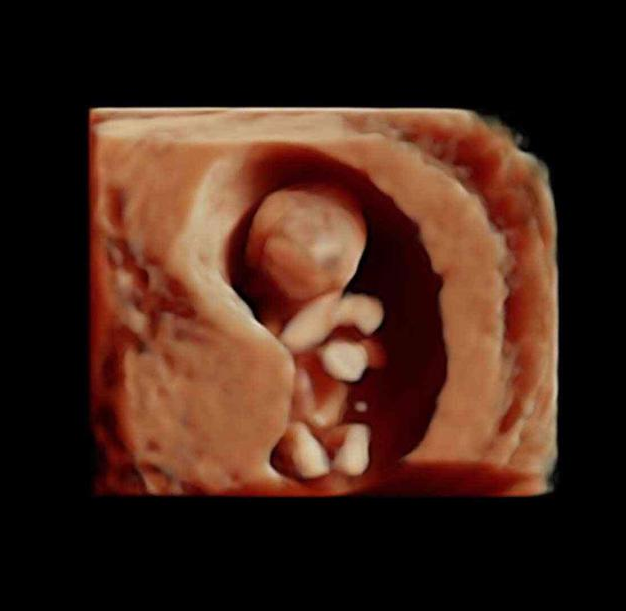

此时的宝宝可以叫做胎宝宝了,因为它已经具备很多人类的特征了,他的各个器官、肌肉和神经系统已经发育的产不多了,顾家也开始越来越坚固,从图片上看,宝宝就是迷你型的胎儿,他的各个器官开始工作了。

进入第10周,胎儿的发育更细致了,比如眼睛和眼睑已经融合,眼睛清晰可见,手臂和胳膊等都很清楚,此时的胎儿开始发阿玉生殖器官,不过肉眼是看不出来性别的。